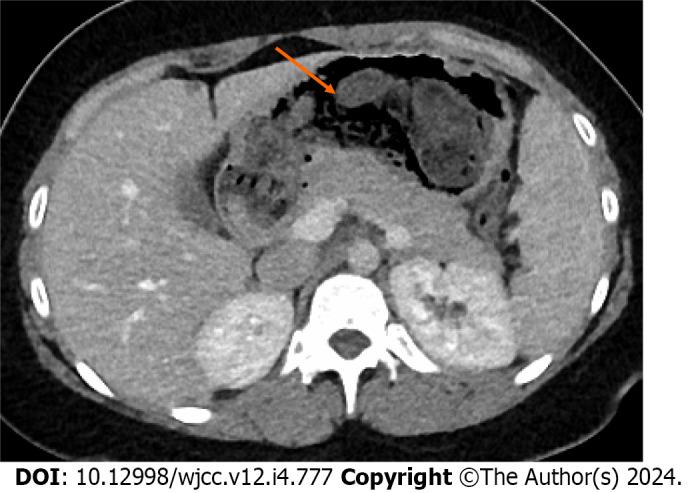

A 24-year-old female patient presented to the emergency room with abdominal pain, nausea, and vomiting for 3 d. Her previous medical and psychiatric history was unremarkable. Laboratory analysis showed iron deficiency anemia, leukocytosis, and elevated liver enzymes. An abdominal CT scan revealed a dense structure in the patients' stomach which turned out to be a huge trichobezoar completely obstructing the pylorus. The trichobezoar had to be removed surgically. During her postoperative course, a subcutaneous seroma formed. After a single puncture, the rest of the recovery process was unremarkable, and the patient recovered fully.

一名24岁女性患者因腹痛、恶心和呕吐3天就诊于急诊室。她既往的内科和精神病史均无异常。实验室分析显示缺铁性贫血、白细胞增多和肝酶升高。腹部CT扫描显示患者胃内有一个致密结构,结果是一个巨大的毛石完全阻塞了幽门。必须通过手术切除毛石。在术后过程中,形成了皮下血清肿。经过一次穿刺后,其余的恢复过程无异常,患者完全康复。